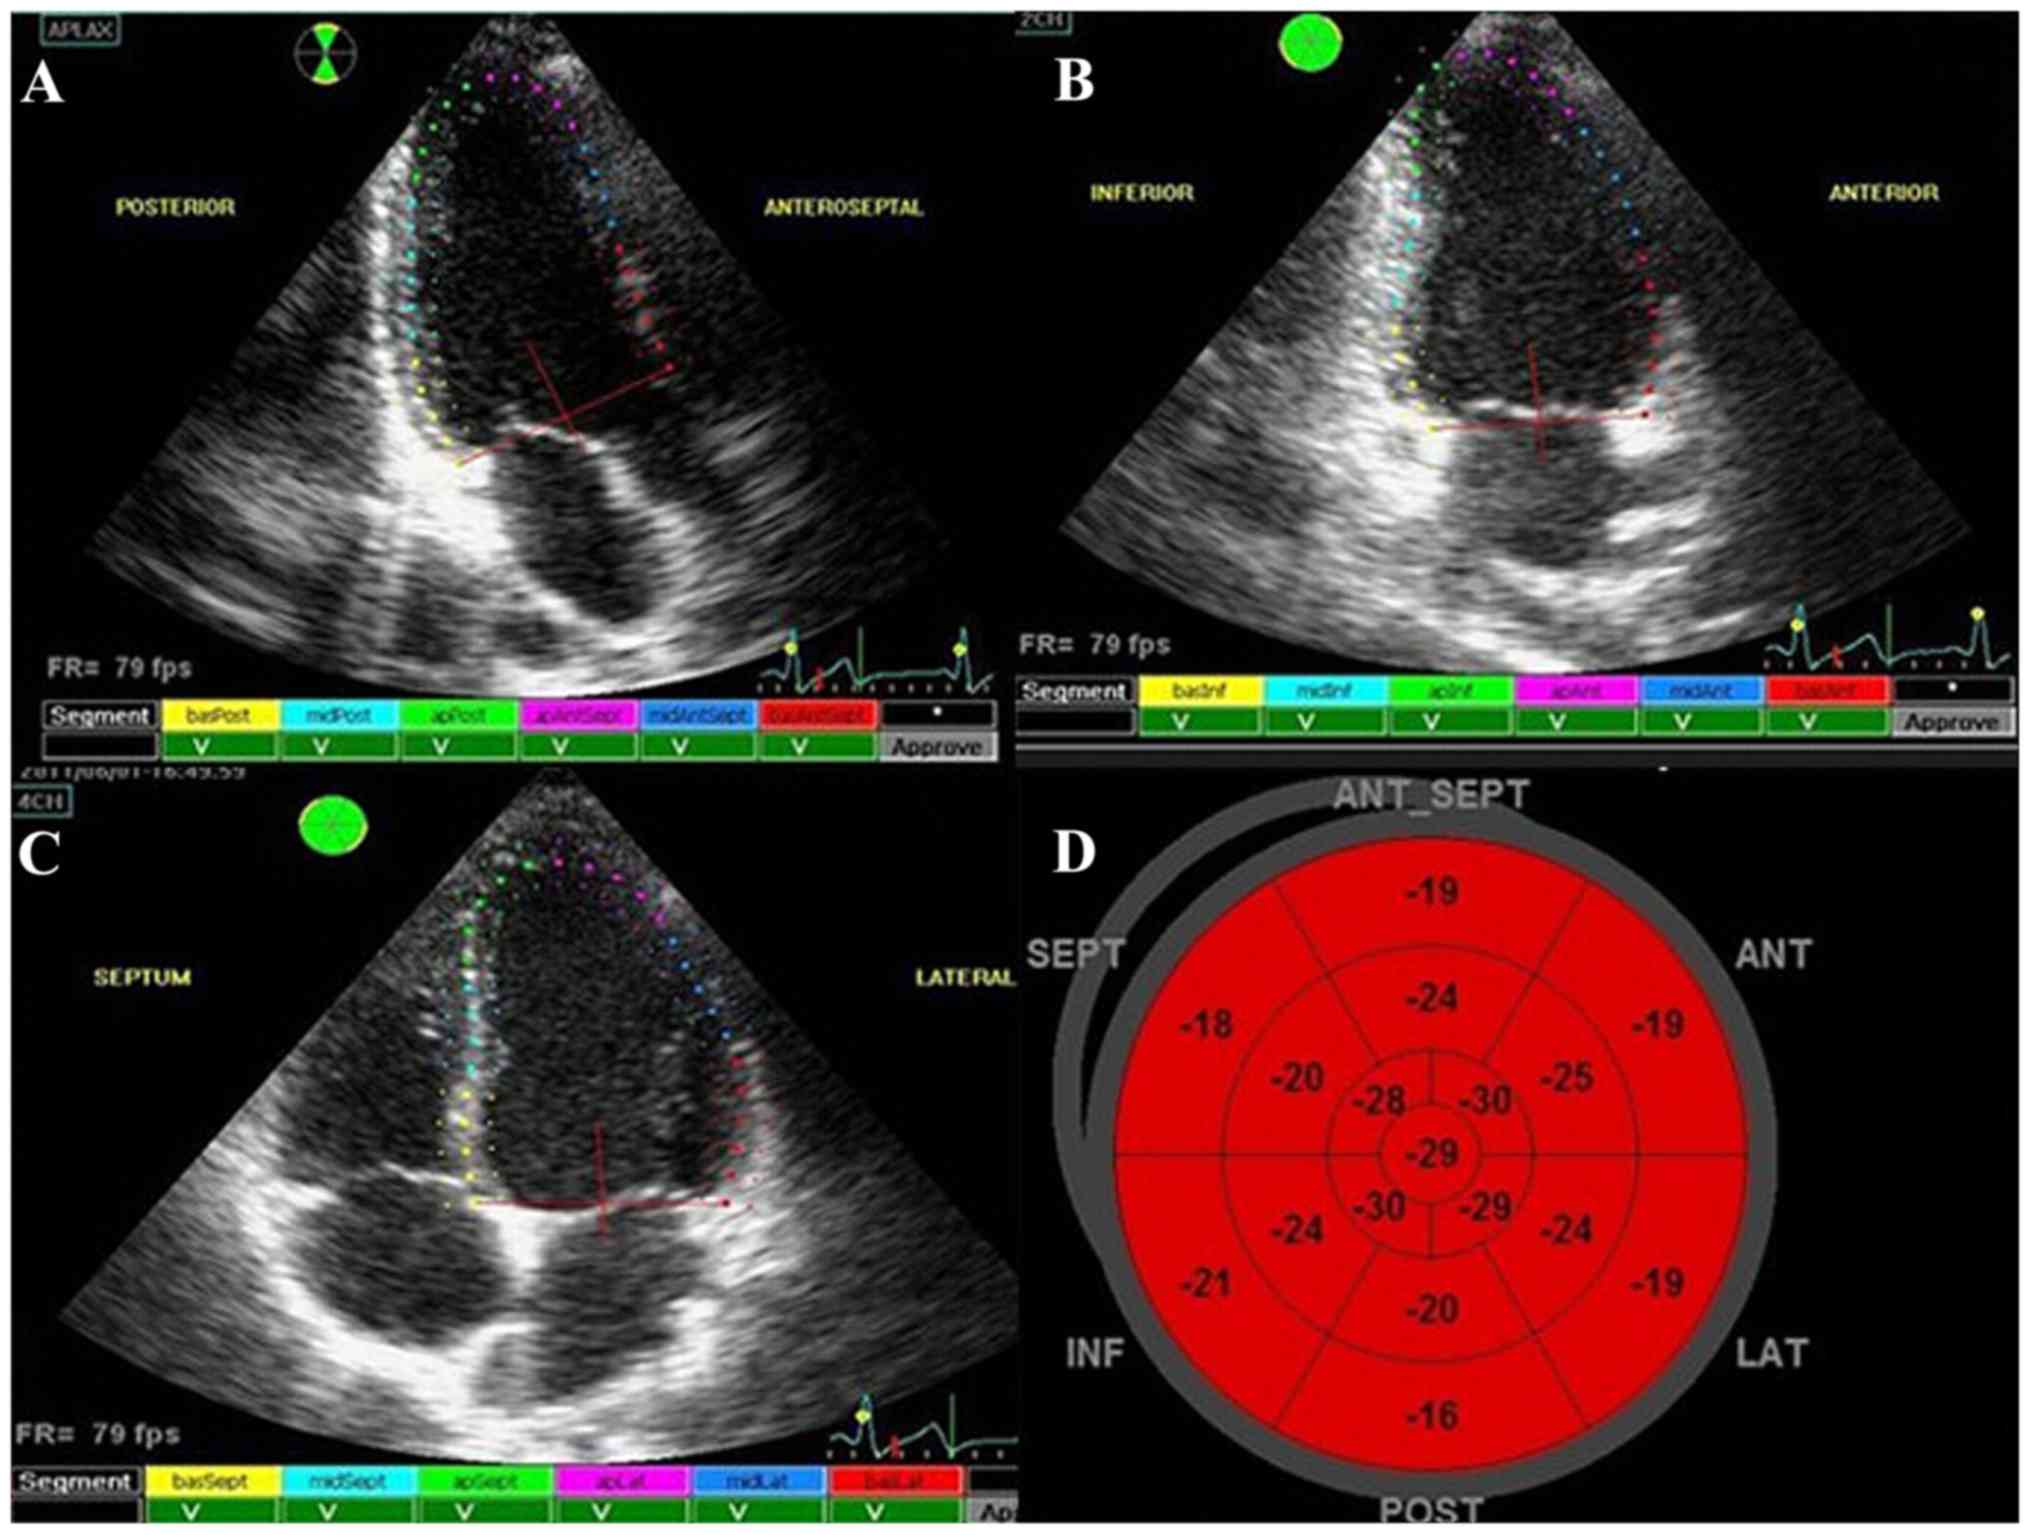

APLAX, 4CH, 2CH, SAX-MV, SAX-PM, and SAX-AP images were obtained by TTDE and stored for off-line analysis. The frame rate range was 40–80 frames/sec. EchoPAC first selected the APLAX section in a cardiac cycle (Fig. 2A) and then, at the advanced systolic stage, the target area between the endocardium and epicardium was automatically or manually drawn at the left ventricular endocardium border. Then, the color strain curve was developed and calculated at the workstation and the left ventricular wall was automatically divided into 6 segments. Then 2CH (Fig. 2B), 4CH (Fig. 2C), SAX-MV, SAX-PM, and SAX-AP were analyzed by the same procedures. Segmentation was completed with reference to the left ventricular myocardial segmentation method proposed by the American Society of Echocardiography (ASE) (11). After analysis, the workstation obtained the long axis, circumference, radial total strain, strain rate (Fig. 3A-D), and long axis target chart of 17 segments (Fig. 2D) (the same as that of target chart of 17 segments by MPI). Existence of myocardial ischemia in patients and the ischemia degree were evaluated by target chart (Fig. 4A-C). The color gradation of the target chart covered eight colors from evenly dark red to evenly dark blue. The strain value range was −20 to 20%. Every color corresponded with five-strain value units (%), indicating the myocardial blood supply condition from the normal level to mild myocardial ischemia, moderate myocardial ischemia, serious myocardial ischemia, and myocardial infarction. We also applied STI color gradation to conduct self-defined evaluation for myocardial ischemia: 0 points (−20 to −16%), dark red; 1 point (−15 to −11%), mild red; 2 points (−10% to 0), mild red and pink; 3 points (1 to 10%), sky blue and mild blue; 4 points (11 to 20%), mild blue and dark blue.

Figure 2.

2D-STI. (A) 3CH speckle tracking. (B) 2CH speckle tracking. (C) 4CH speckle tracking. (D) 2D-STI normal target chart. 2D-STI, two-dimensional speckle tracking imaging.